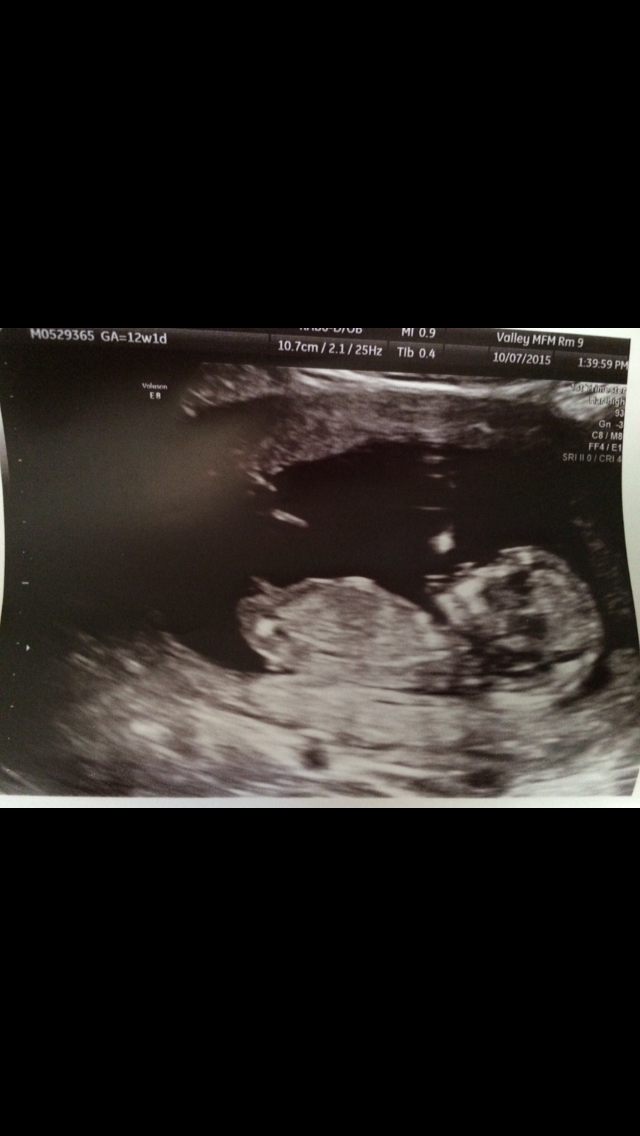

This ultrasound was done at 9w 3d. 12w 1d today . Wish I would have had one done a little further along to see something more . Fhr at 173 bpm. This is baby #2 we're really stoked

12w 1d today . Wish I would have had one done a little further along to see something more . Fhr at 173 bpm. This is baby #2 we're really stoked